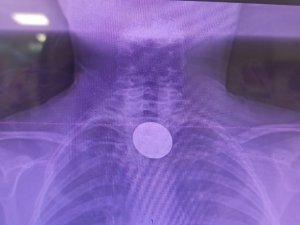

Madeni paranın yemek borusuna kadar indiği tespit edildi

Yapılan incelemelerde 5 TL’lik madeni paranın Y.K.’nin yemek borusuna kadar ilerlediği belirlendi. Çocuk hastalarda ciddi solunum ve sindirim sistemi riskleri oluşturabilen bu durum üzerine ilgili branşlar vakit kaybetmeden harekete geçti.